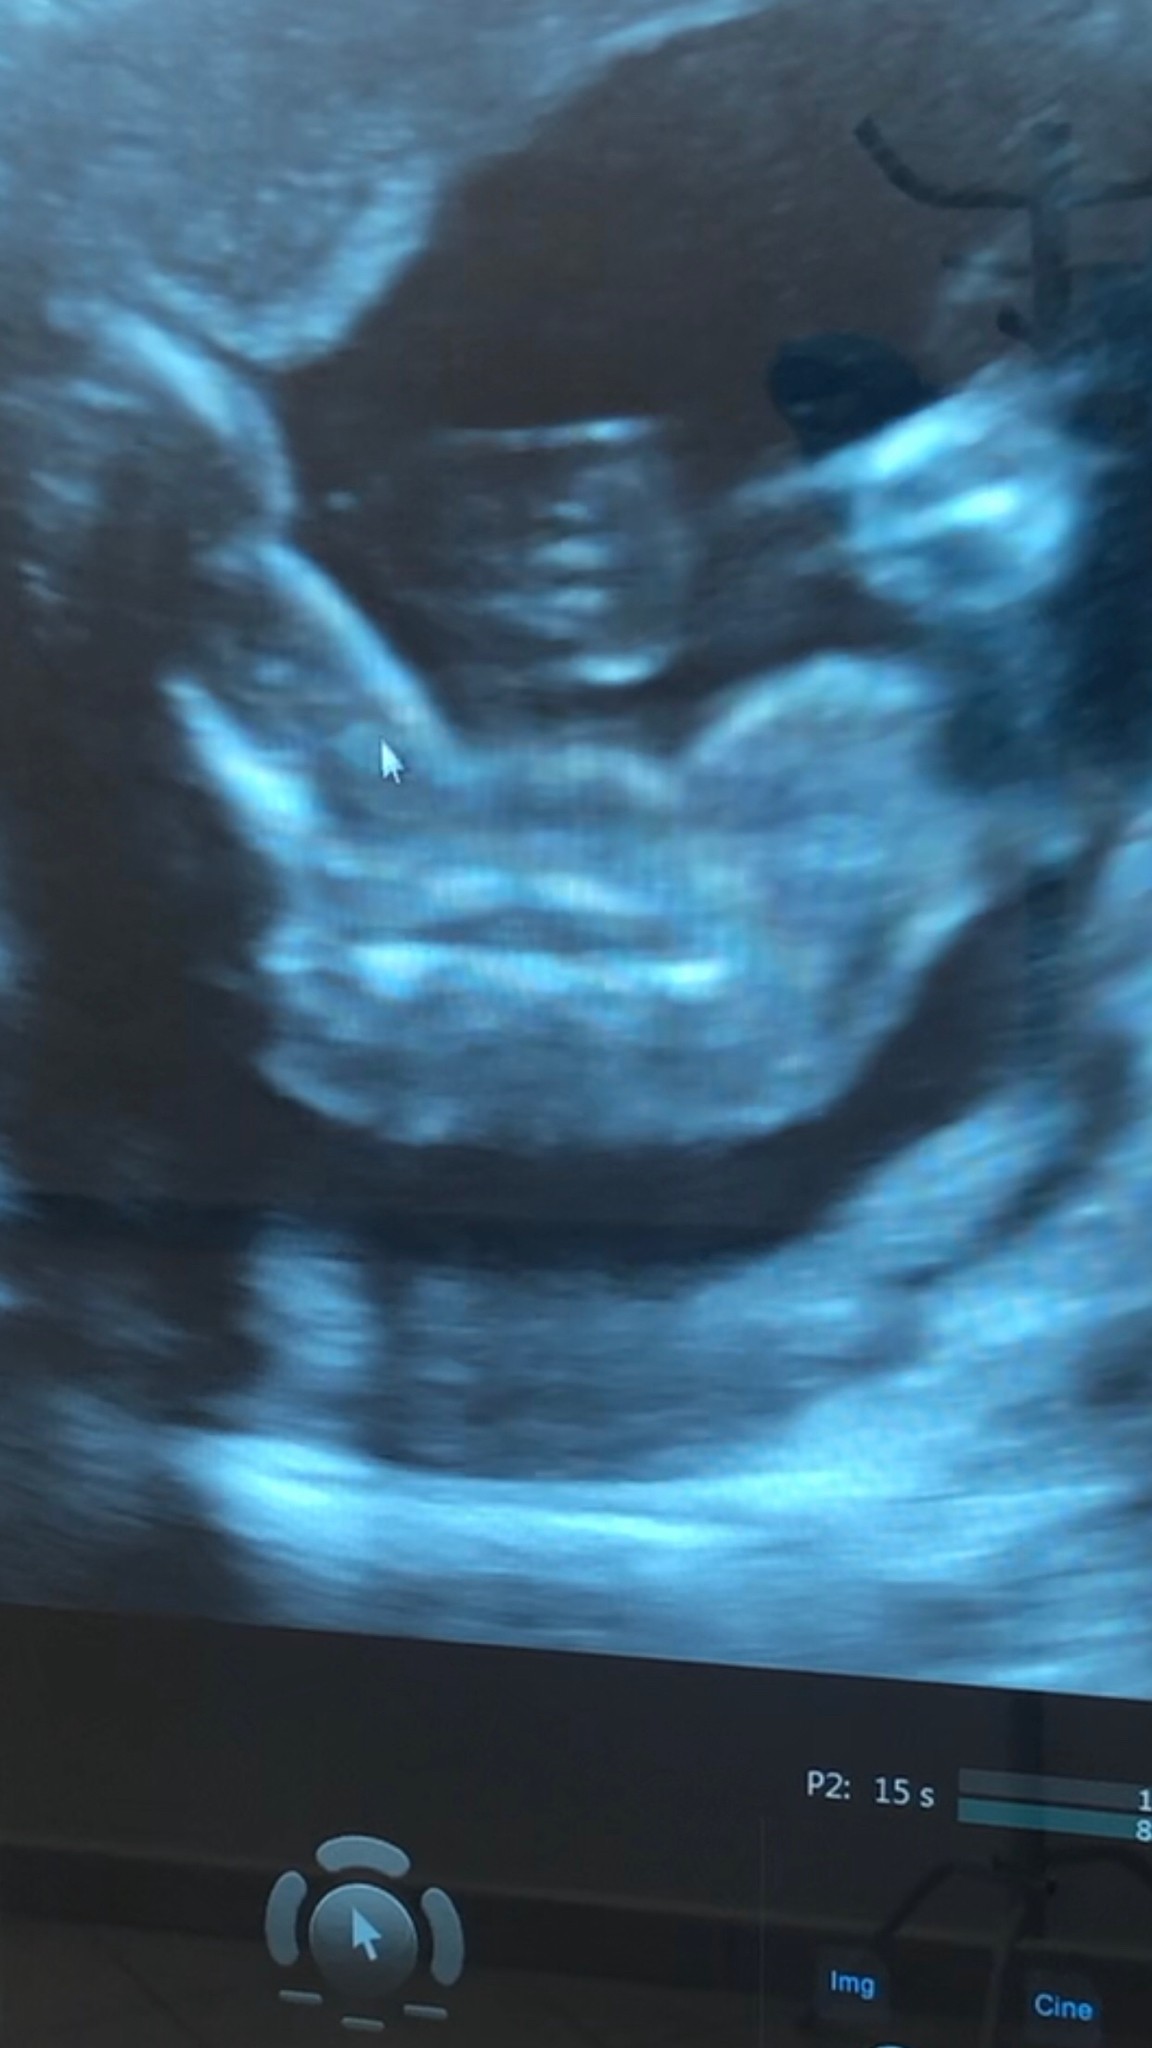

@martoosia04 jak dla mnie dziewczyna bo nic nie widać pomiędzy nóżkami. Gratuluje !

A lekarz w końcu potwierdził nasze prorokowania ?

Potwierdził, że nic nie widać (czyt. nie ma siurka) ale poleca świętować po połówkowych gdzie będzie widać wyraźniej na lepszym sprzęcie. Ale ja swoje widzę ;)

IMG_3758.JPG